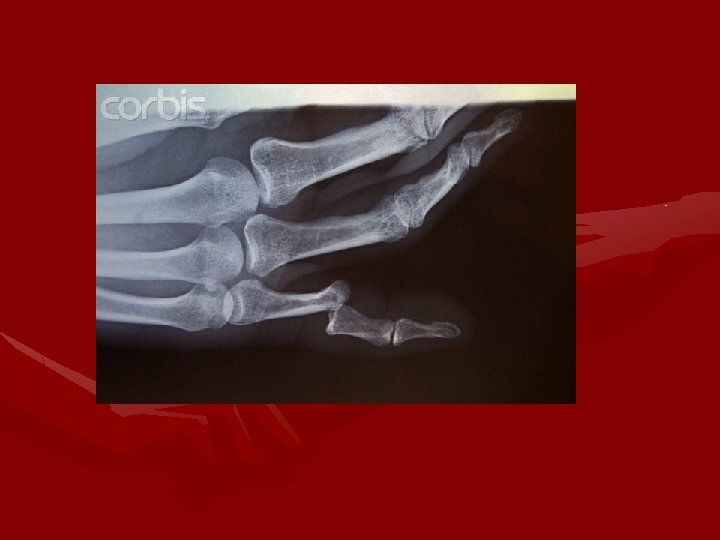

Metacarpal (Boxer’s) Fracture • Most common of all metacarpal fractures • Associated with martial arts/boxing • MXN: • direct axial force caused by punching another person or object • Direct impact to hand

Boxer’s fracture

• S/S: • POT over the metacarpal involved • Palpable defect in the shaft of the 5 th metacarpal (or other metacarpals) • Swelling • Discloration • Pain with movement

Metacarpal fractures